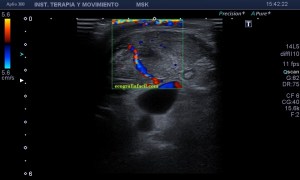

4

Se demostró lo que ya presentía, que era la vascularización típica de un vaso, vaso que resultó ser uno de alto flujo, y  te explico…cuando estudiamos una malformación vascular por ecografía, podemos encontrarnos malformaciones de bajo flujo, las venas, de alto flujo, arterias o mixtos de ambas.

5

En la imagen 5 ves el típico aspecto de un vaso de alto flujo, lo normal, ya que tenía latido. Vas a ver dicho espectro con aspecto de picos y valles muy marcados, el sonido también es diferencial, puedes ver el doppler espectral y escucharlo. Su sonido y su aspecto es distinto del de una vena.

En este caso debí usar una muestra, flecha amarilla de la imagen 5, lo más pequeña posible, ya que el vaso lo era igual, adaptaremos esta muestra al tamaño del vaso que quieras estudiar. si la muestra no es la idónea la lectura puede ser incoherente. La muestra es el tamaño del «roi2 que hará el registro de la zona a estudio. Te enlazo arriba para que revises nociones básicas de doppler en post anteriores, también puedes consultar el índice del blog al final de este Post.

En este vídeo puedes ver como en la imagen 2D  como late la estructura, y como con el doppler color la vascularización es evidente. Puedes estudiarlo con Triplex, en el enlace a instagram ves como se estudia la lesión con una técnica de la que ya te he hablado más veces, donde puedes ver el doppler color y el espectral a la vez, eso sí, consumieno muchos recursos del equipo.

El diagnóstico final del radiólogo fue psudoaneurisma de la arteria palmar del segundo dedo.